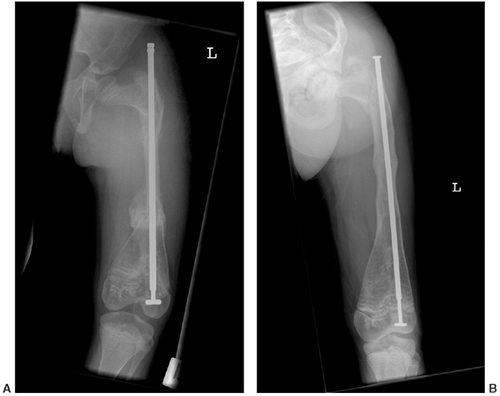

![]() |

Figure 7.9 This female infant with severe osteogenesis imperfecta (OI) presented at 19 months of age with a left femoral fracture (A) which was treated in a spica cast and healed (B). A refracture was treated in a spica (C) with progressive varus. At age two, a second refracture occurred through the varus malunion (D) and was treated with open intramedullary (IM) Williams rodding (E).

Three years later the femur is intact and has grown distally, as evidenced by the position of the rod and by the transverse metaphyseal lines that occur with each pamidronate treatment cycle (F). |